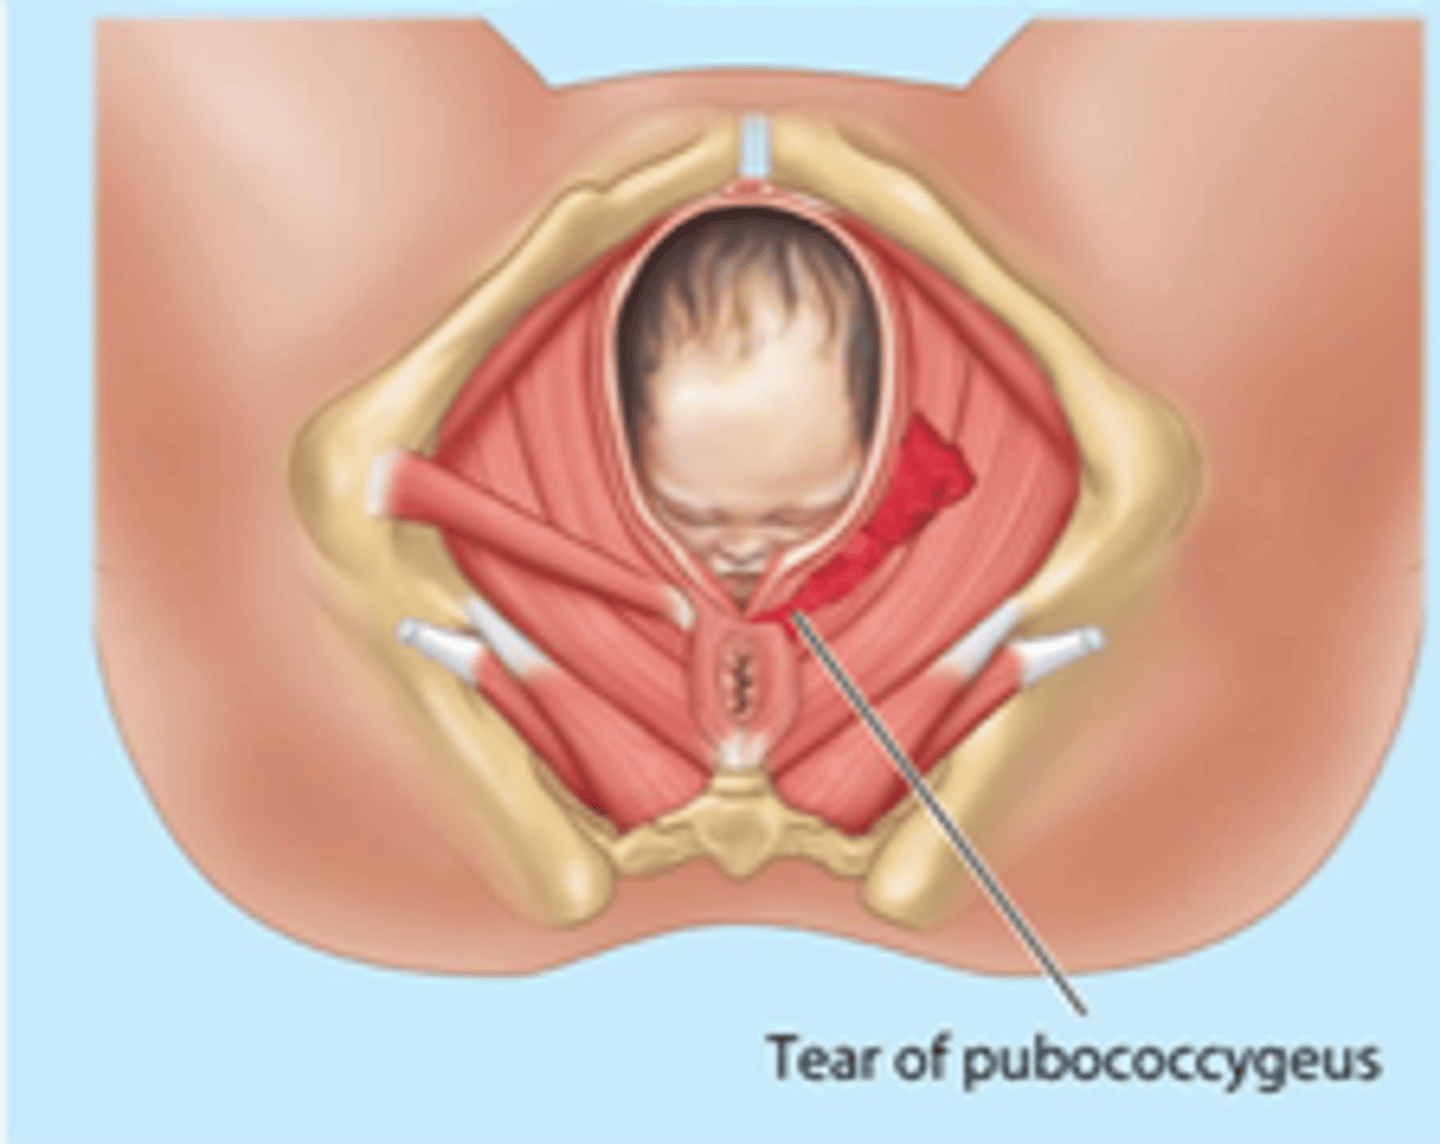

pelvic floor injury

-extremely common consequence of vaginal delivery

-puborectalis and pubococcygeus are most common muscles damaged, causing incontinence and sexual dysfunction